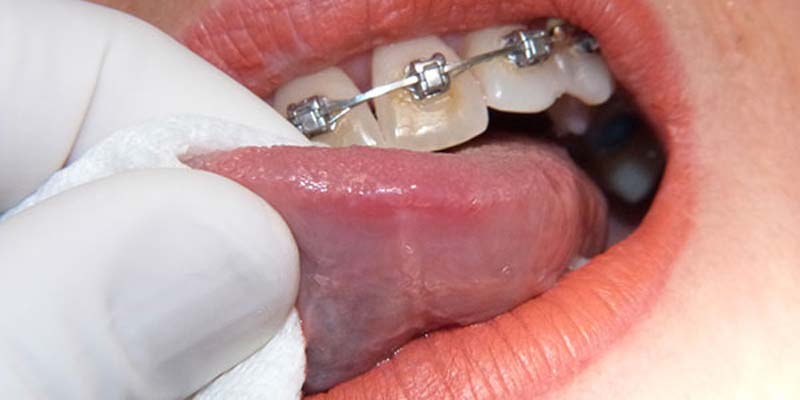

Le afte della bocca , rientranti nel capitolo delle cosiddette stomatiti, processi infiammatorii che coinvolgono la cavità orale e la mucosa della bocca, sono probabilmente, insieme all'herpes labiale, le forme, appunto, di stomatite più contratte. Si presentano come piccole lesioni della mucosa della cavità orale (guance, labbra e, talvolta, anche sulla lingua) che hanno l'aspetto di piccole ulcerazioni biancastre, di forma tondeggiante, che sono spesso causa di bruciori e forti dolori, in particolare durante l'atto masticatorio. Nella grande maggioranza dei casi le lesioni aftose si presentano isolate ma, sporadicamente, possono presentarsi anche in piccoli gruppi ed associarsi a sintomi quali febbre, ingrossamento dei linfonodi ed anche sintomi influenzali.

Si distinguono clinicamente una forma “ Minor” , caratterizzata da lesioni di piccola dimensione , in genere non superiori ad un cm che si localizzano generalmente a livello della mucosa orale non cheratinizzata, (vestibolo orale, ventre linguale, pavimento orale, mucosa labiale). La guarigione è spontanea e avviene con restituito ad integrum dei tessuti in un paio di settimane dall’esordio, ed una forma “ Major”, in cui le ulcere hanno un diametro che può raggiungere e superare il centimetro, guariscono in tempi più lunghi rispetto alle afte minor e spesso lasciano una cicatrice, la mucosa interessata è quella del palato o del dorso linguale. Come già accennato le afte vanno incontro ad una guarigione spontanea nel giro di sette dieci giorni e il trattamento, ad oggi , è indirizzato al solo scopo di ridurre la sintomatologia e abbreviare il decorso delle lesioni; si avvale classicamente dell’utilizzo di preparati per uso topico a base di corticosteroidi, di aloe, di sodio jaluronato e aminoacidi o di antisettici (per evitare la sovrainfezione della mucosa lesionata). Un’arma in più è rappresentata dall’uso del laser a diodi , che ha dimostrato di ottenere ottimi risultati , grazie alla sua capacità di sterilizzazione dei tessuti infetti e di stimolazione del processo di guarigione, tale cherisulta essere, attualmente, lo strumento ideale per la terapia di queste dolorosissime lesioni, che, se trattate nel giro di 24 ore o poco più, hanno una rapidissima remissione ed un’immediata riduzione della sintomatologia dolorosa.